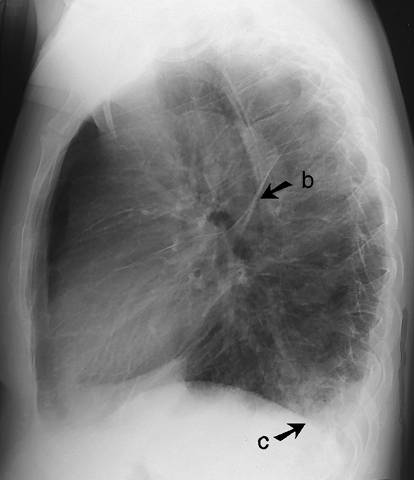

Interstitial oedema in the lungs (lateral view). Interstitial oedema in the lungs (lateral view). Oedema is also accumulated along the lobe margins (b) and in the scars. The condition is often associated with pleural fluid (c). For PA view: see Interstitial Oedema in the Lungs (Pa View).